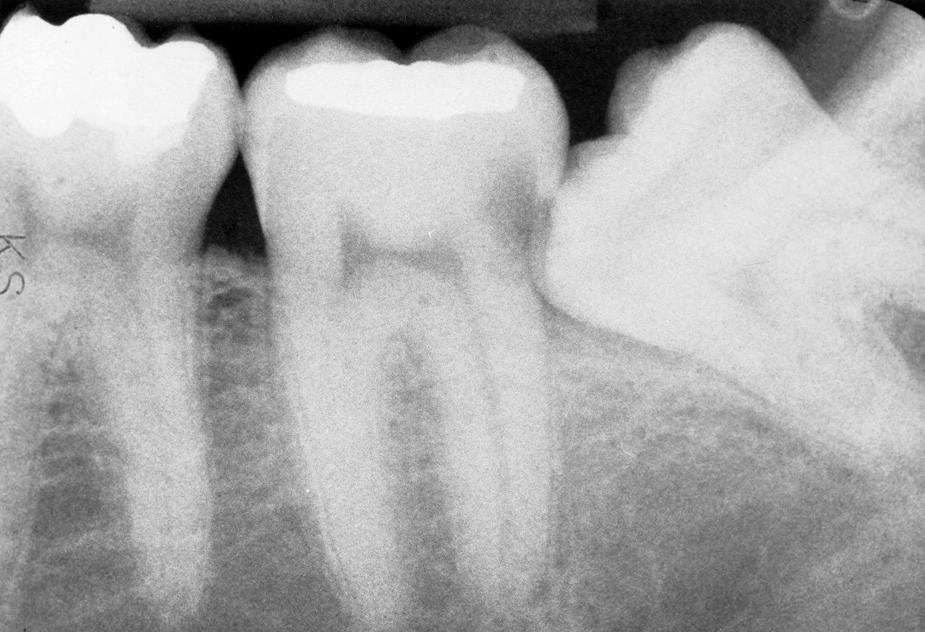

When a third molar is impacted or partially impacted, the bacteria and other factors that cause dental caries are commonly exposed to the distal aspect of the second molar as well as to the crown of the impacted third molar. Even in situations in which no obvious communication between the mouth and the impacted third molar is visible, there may be enough communication to allow for caries initiation ( Figs. 10.3 to 10.5 ).

Fig. 10.3, Radiograph of caries in a mandibular second molar resulting from the presence of an impacted third molar.

Fig. 10.4, Radiograph of caries in a mandibular impacted molar.

Fig. 10.5, Radiograph of caries in an impacted third molar and a second molar.